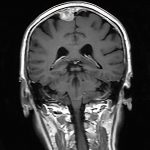

218

'21年9月

80代

左後頭頂葉腫瘤

頭蓋内腫瘍摘出術

No.’21_62 手術前1

No.’21_62 手術前2